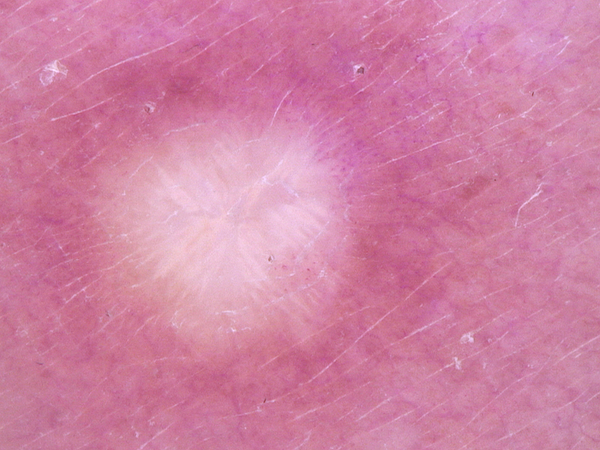

Dermatofibroma